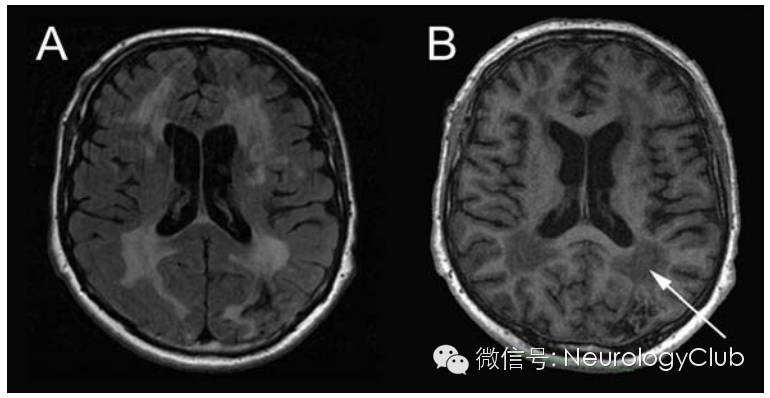

(CSVD的重要影像学特征。A:DWI提示急性深部小梗死[腔隙性梗死],直径<2cm;B:FLAIR上提示腔隙,内为脑脊液,直径在3mm-1.5cm之间,位于白质或深部灰质或者脑干,信号同脑脊液;C:FLAIR提示白质高信号,见于白质和深部灰质以及脑干,呈T2/FLAIR高信号,T1WI多不可见但偶为低信号,数量较多时可融合;D:T2WI提示血管周围间隙,因内为脑脊液样液体故而呈高信号,直径<3mm,圆形或线形,位于白质和深部灰质,明显时T1上可见低信号)

(A:T1WI腔隙灶;B:FLAIR脑白质 病变;C:T2*WI微出血;D:T2WI扩大的血管周围间隙)